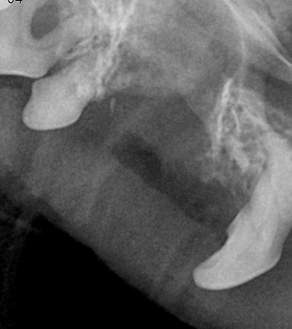

BEFORE

AFTER